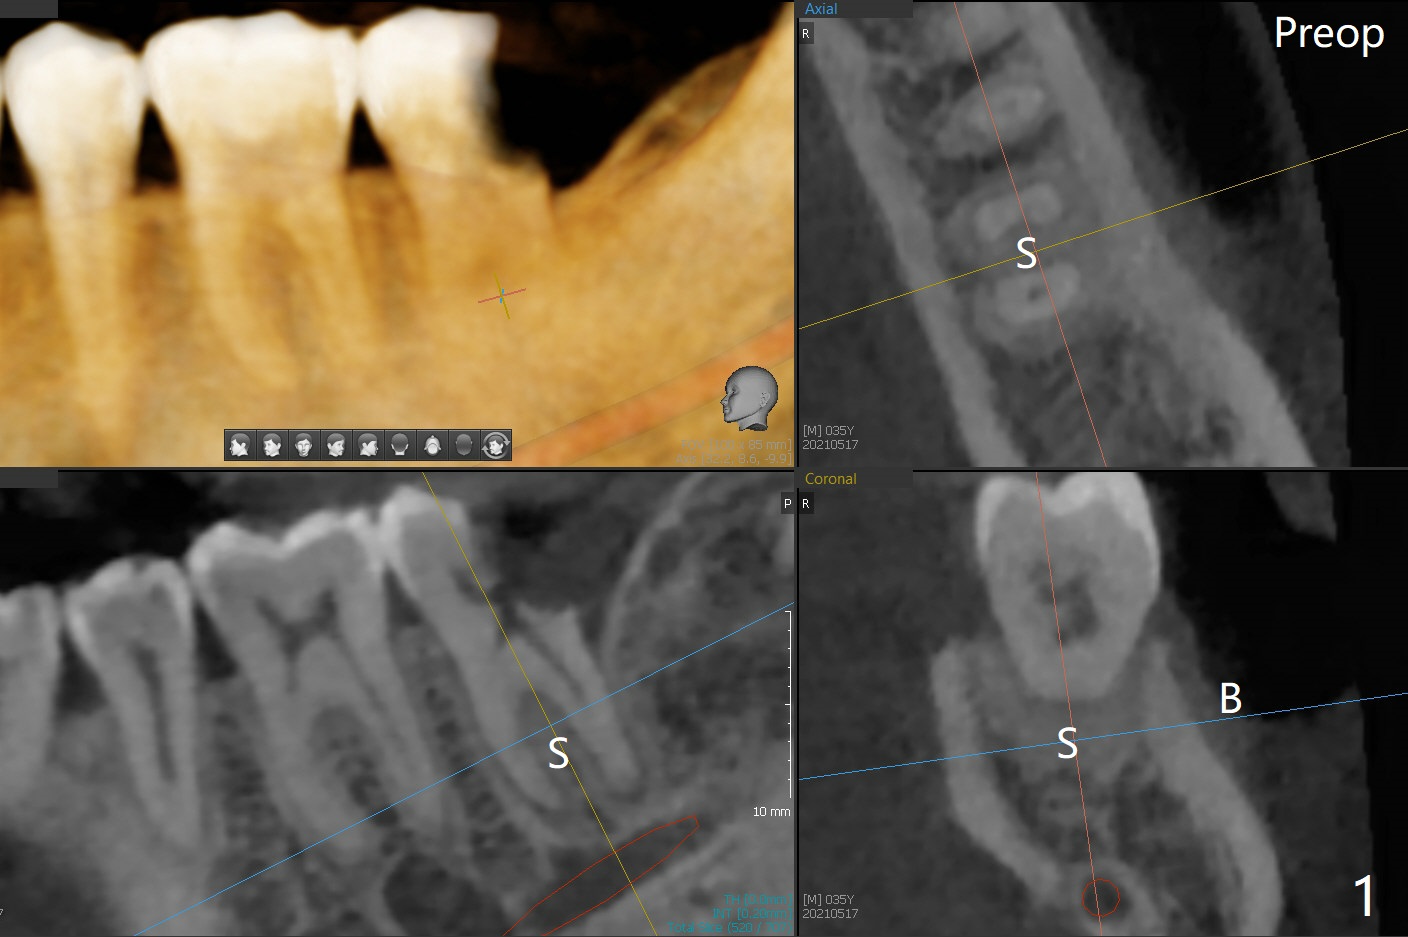

18号牙远中龈下龋齿,在导板指引下,使用4.0x8.5毫米钻头后,钻洞建立在中隔(图一:S)近中舌侧,5.0x9毫米植体似乎还没有超出牙槽窝轮廓(图二),已经取得35Ncm扭力。放置基台后,放入足够粘性骨粉(图三:*),然后制作临时牙冠,结合PRF,固定骨粉。由于植体没有接触牙槽嵴,那里骨质吸收将是轻微的,而骨质再生显著。